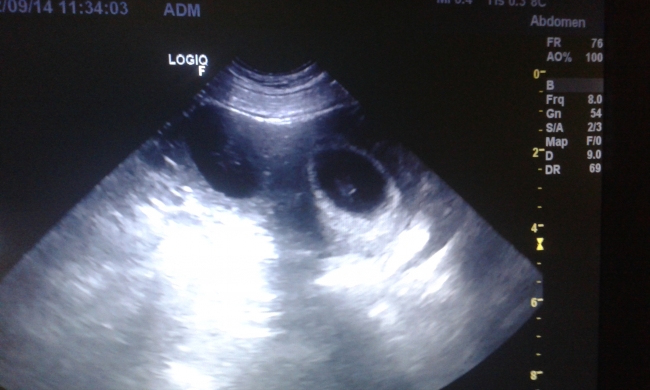

Wczorajszy dzien dal mi niezlego "kopa " z adrenaliny :mrgreen: zapowiadalo sie ze jesien bedzie jak to jesien dosc szara i ponura, bo ta złota to zazwyczaj omija nas duuuzym lukiem ;-) az tu wczoraj kontrolne badanie wykazalo ze male Soulberniatka za niedlugi czas wypelnia, pelnia zycia , szare jesienne wieczory :okok:

Maluszki Bibuły i Ferdusia :love:

obrazek

Obrazek został zmniejszony.

A tu maluszki Fibulca i .... szczegóły w krótce :love: :-D

Nadal nie moge uwierzyc w to co przed nami.... :radocha: